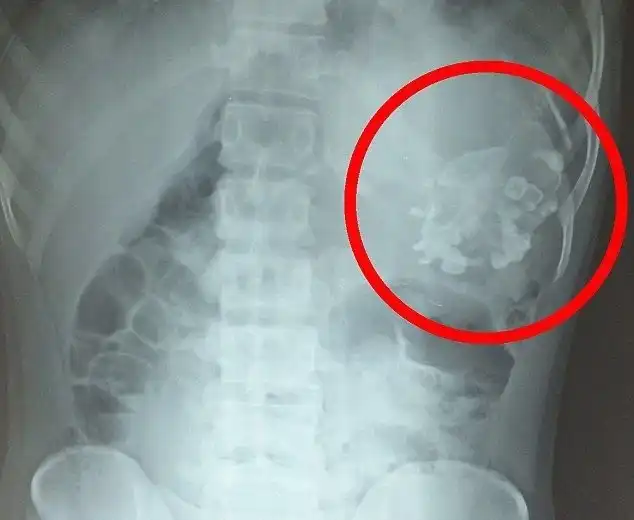

18-летний Нарендра Кумар с детства страдал всевозможными недомоганиями и потерей веса. Его родители были вынуждены обратиться к врачам, когда его состояние стало совсем скверным. Причиной тому оказался близнец-паразит с зубами и волосами, прятавшийся внутри пацана.